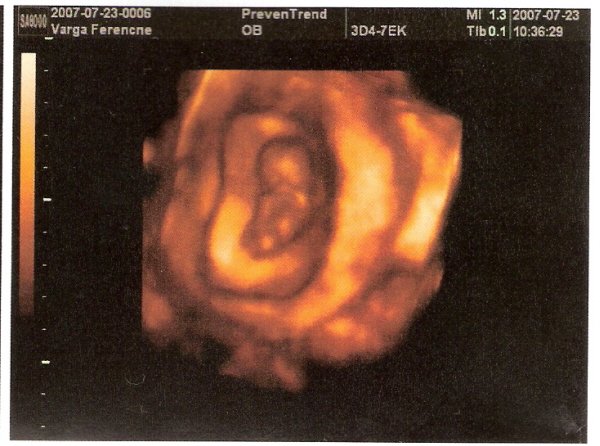

Annyira örülök a jó eredmény miatt, na meg persze az miatt is, hogy kislány a drága.